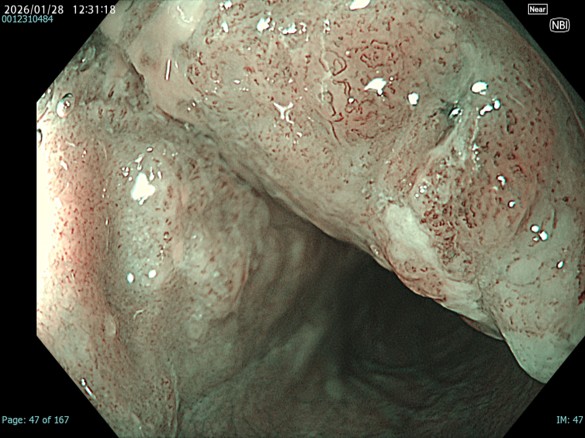

• NBI観察(拡大)

強調設定:A8

図14

NBI-mode、Near-focus拡大。関心領域になるであろう瘢痕部分の拡大観察ではループ構造が崩れたB2血管を認めます。